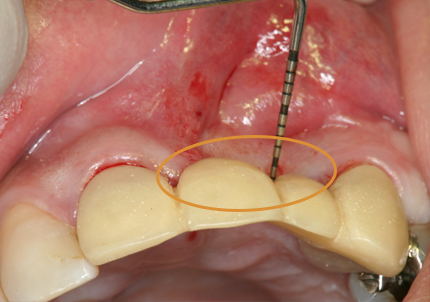

4.右上2番 S.S.T(ソケットシールドテクニック)

5.左上1番 S.S.T(ソケットシールドテクニック)

6.左上2番 S.S.T(ソケットシールドテクニック)